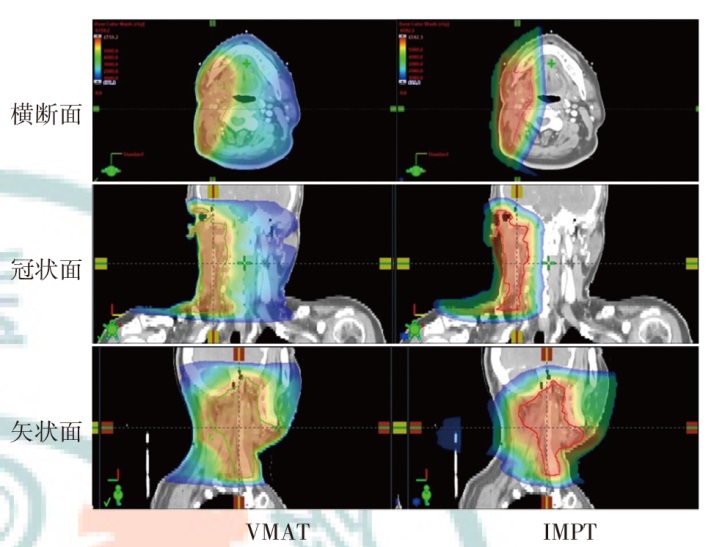

Objective To investigate the dosimetric characteristics of intensity modulated proton therapy (IMPT) and photon volumetric modulated arc therapy (VMAT) in typical head and neck malignant tumors. Methods Three types of typical head and neck tumors (nasopharyngeal carcinoma, parotid gland carcinoma, laryngeal carcinoma) treated at Shandong Cancer Hospital and Institute from December 2023 to December 2024 were taken as research subjects. IMPT and VMAT radiotherapy plans were created according to clinical prescription requirements of target and organs at risk limits respectively. The conformity index (CI), homogeneity index (HI) and gradient index (GI) for target coverage of two radiotherapy plans were evaluated for 3 patients, as well as the dosimetric indicators of organs at risk. Results The CI of IMPT for nasopharyngeal carcinoma, parotid gland carcinoma and laryngeal carcinoma were 0.70, 0.72 and 0.67, respectively. The HI were 0.11, 0.08 and 0.08, respectively. The GI were 3.08, 2.49 and 3.75, respectively. The CI of VMAT plans were 0.77, 0.82 and 0.91, respectively. The HI were 0.12, 0.10 and 0.04, respectively. The GI were 3.67, 2.63 and 3.45, respectively. The results showed that CI of IMPT plan was slightly lower than that of VMAT plan, and HI of IMPT plan was comparable to that of VMAT plan, the GI of the IMPT plan for patients with nasopharyngeal carcinoma and parotid gland carcinoma was lower than that of the VMAT plan, and the GI of the IMPT plan for patient with laryngeal carcinoma was higher than that of the VMAT plan, and all were within the clinically acceptable range. The IMPT plan has demonstrated significant dose advantages in the treatment of nasopharyngeal carcinoma, parotid gland carcinoma and laryngeal carcinoma. For patient with nasopharyngeal carcinoma, the IMPT plan reduced the Dmax of the left and right crystals by 54.1% and 50.4%, respectively, compared to VMAT plan, and reduced the Dmean of the oral and laryngeal tissues by 40.5% and 49.6%, respectively. For patient with parotid gland carcinoma, IMPT plan reduced the Dmax of the brainstem and spinal cord by 66.2% and 40.5%, respectively, compared to VMAT plan. For patient with laryngeal carcinoma, IMPT reduced spinal cord Dmax by 77.0%, while thyroid cartilage Dmean increased by 8.0% compared to VMAT plan. For the additional dose in the patients' body, taking the absolute volumes occupied by the prescribed dose areas of 10%, 30%, and 50% in the patients' body as examples, IMPT plan of nasopharyngeal carcinoma patient decreased by 29.7%, 29.6%, and 34.9% compared to VMAT plan, respectively. IMPT plan of parotid gland carcinoma patient decreased by 61.0%, 39.7%, and 17.4% compared to VMAT plan, respectively. IMPT plan of laryngeal carcinoma patient decreased by 63.9%, 31.7%, and 4.1% compared to VMAT plan, respectively. Conclusions Compared with VMAT plan, IMPT plan can effectively reduce the irradiation dose of most organs at risk near the target of head and neck tumors, but the dose of string organs close to the target area may be higher, which needs attention.